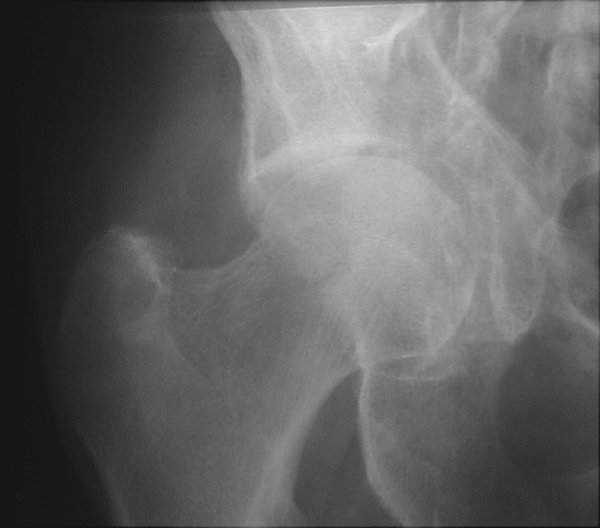

Return to Acetabular Fracture